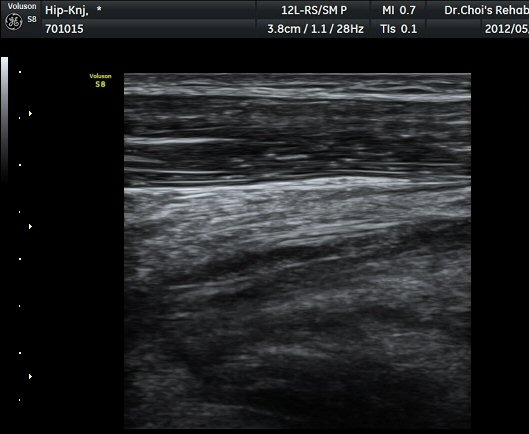

µÚÂÊ ´ëÅð ³»Ãø Ⱦ´Ü¸é°Ë»ç¿¡¼­ À̵ιڱ٠ÀåµÎ ¿ÜÃø¿¡¼­ ±ÙÀ°¼¶À¯¿Í ±Ù¸·¿¡ ÀÇÇØ Çü¼ºµÇ´Â

Á¤»óÀûÀÎ ±ÙÀ°ÀÇ ¸ð¾çÀÌ ¼Ò½ÇµÇ°í Àú¿¡ÄÚ º´º¯À¸·Î °üÂûµÈ´Ù(±×¸² 6). ŽÃËÀÚ¸¦ Á¶±Ý ¸»´ÜÀ¸·Î